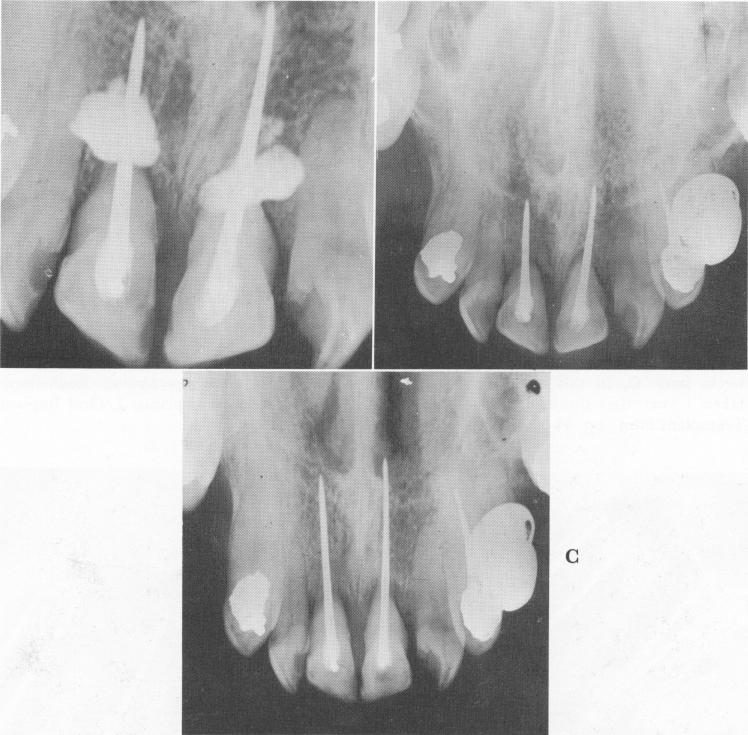

Fig. 13-61. A, A great amount of excess cement was pushed apically beyond the bore holes. In order to prevent irritation and severe inflammation, the cement had to be removed immediately by incising the mucoperiosteal tissue, reflecting it, and curetting it. B, Eighteen months later. C, Five and a half years later. (From Orlay, H. G.: Endodontic implants, J. Oral Implant Transplant Surg., pp. 44-53, 1965.)

1 Excess amount of cement pushed apically beyond bore holes in maxilla